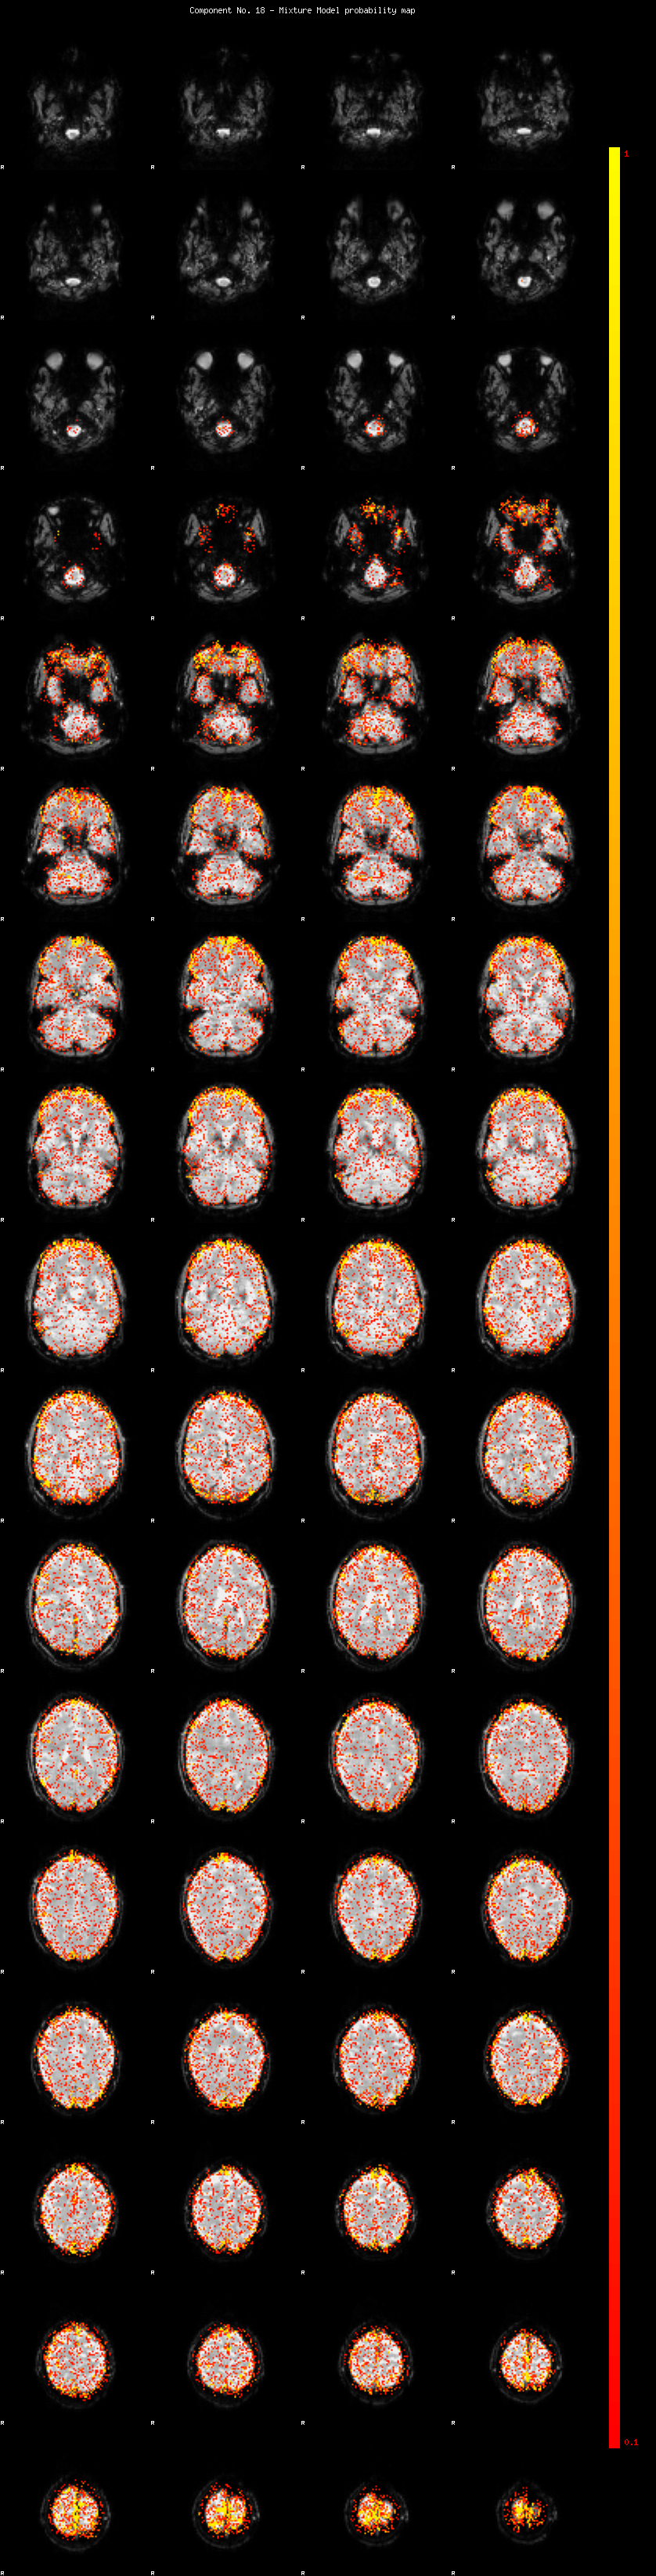

IC_18 Mixture Model fit

Means : -0.000000 2.664149 -2.328556

Vars : 1.000000 2.487326 1.498288

Prop. : 0.896014 0.062055 0.041931